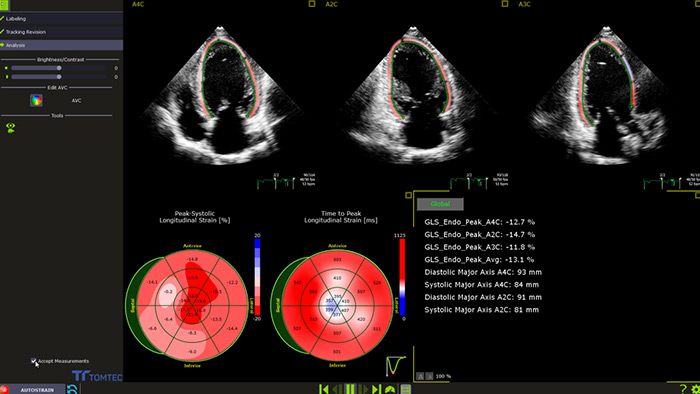

Automatische GLS-Messung für die klinische Routine-Anwendung

Die in das Verfahren integrierte oder bei der Nachverarbeitung angewendete Funktion AutoStrain bietet eine einfache und schnelle GLS-Messung mittels Auto View Recognition und Auto Contour Placement. AutoStrain LV basiert auf einer Lernkurve von mehr als 6000 Bildern und bietet somit Zuverlässigkeit und eine reproduzierbare linksventrikuläre Strain-Messung bei der täglichen klinischen Anwendung.